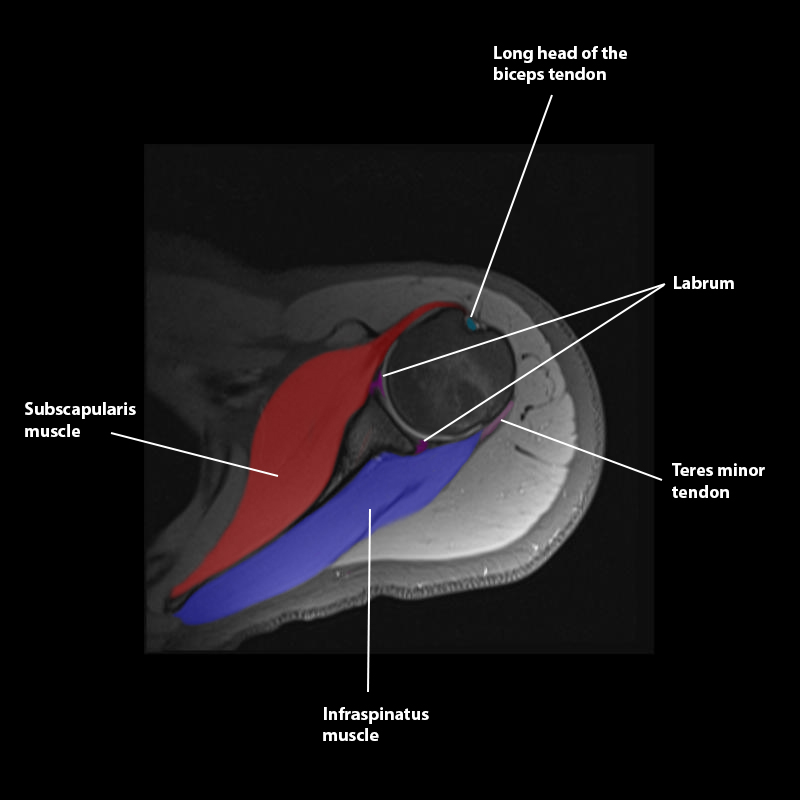

Shoulder MRI Anatomy